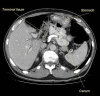

Foramen of Winslow hernia is a rare surgical entity with very few reported cases in literature. Preoperative diagnosis used to be difficult but with emerging computed tomography technology, diagnosing this internal abdominal hernia has become easier. We present an unusual case report of foramen of Winslow hernia in a 77-year-old patient who presented with severe abdominal pain. The patient underwent laparoscopic repair of the hernia and recovered well postoperatively. This presentation of symptoms in a 77-year-old male is unusual and laparoscopic management of foramen of Winslow hernia presents an interesting and challenging management scenario.